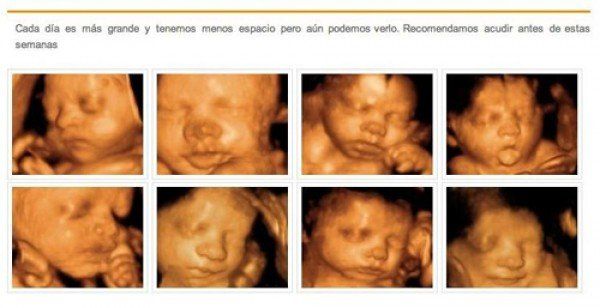

Conozca el excelente trabajo que desarrollamos en relación a la medicina fetal. Realizamos ecografía temprana del embarazo, crecimiento del embrión, entre otros servicios.